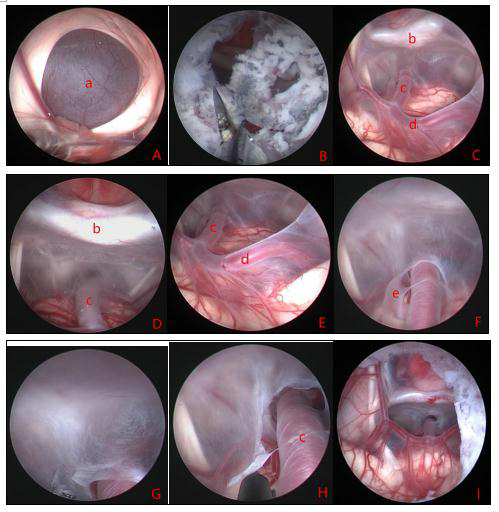

Neurosurgical Oncology Ward 3Neurosurgical Oncology Ward 3 (Middle-line skull base tumors and neuroendoscopy) Specialized features The Neurosurgical Oncology Ward 3 is characterized by the clinical application of neuroendoscopic technology. The annual number of neuroendoscopic surgeries exceeds 1200, and the quantity and quality of neuroendoscopic surgeries are leading domestically and internatio…